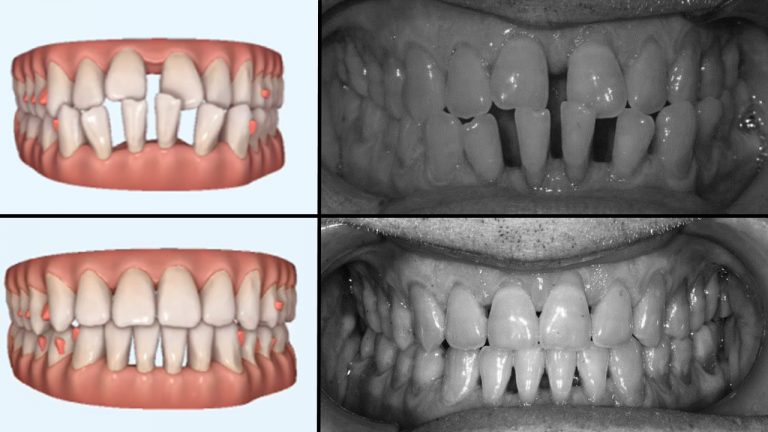

הכנה לשתלים

במבוגרים הזקוקים להשתלת שיניים עקב עקירה או חסר של שיניים קבועות, ישנה פעמים רבות בעיה של מקום לביצוע השתל.